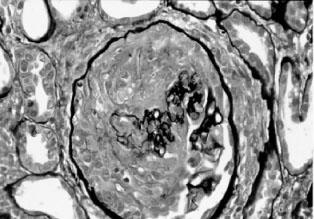

镜下主要病理改变为肾小球壁层上皮细胞增殖,广泛性(50%以上)上皮细胞新月体形成,充满肾小球囊腔(占据肾小球囊腔50%以上),致使囊腔闭塞(图2—4)。病变早期为细胞新月体,后期为纤维新月体。肾小球周围有中性粒细胞、单核细胞、淋巴细胞浸润,肾小球系膜细胞及内皮细胞也可明显增生。另一少见类型为开始时肾小球毛细血管丛坏死病变,肾小球几乎完全破坏,继之被瘢痕组织所代替,而肾小球囊腔之新月体数目和程度都较轻。免疫病理学检查是分型的主要依据,Ⅰ型IgG及C3呈光滑线条状沿肾小球毛细血管壁分布;Ⅱ型IgG及C3呈颗粒状沉积于系膜区及毛细血管壁;Ⅲ型肾小球内元或仅有微量免疫沉积物。电镜下可见Ⅱ型电子致密物在系膜区和内皮下沉积,Ⅰ型和Ⅲ型无电子致密物。

图2—4 新月体性肾小球肾炎(PASM x400)